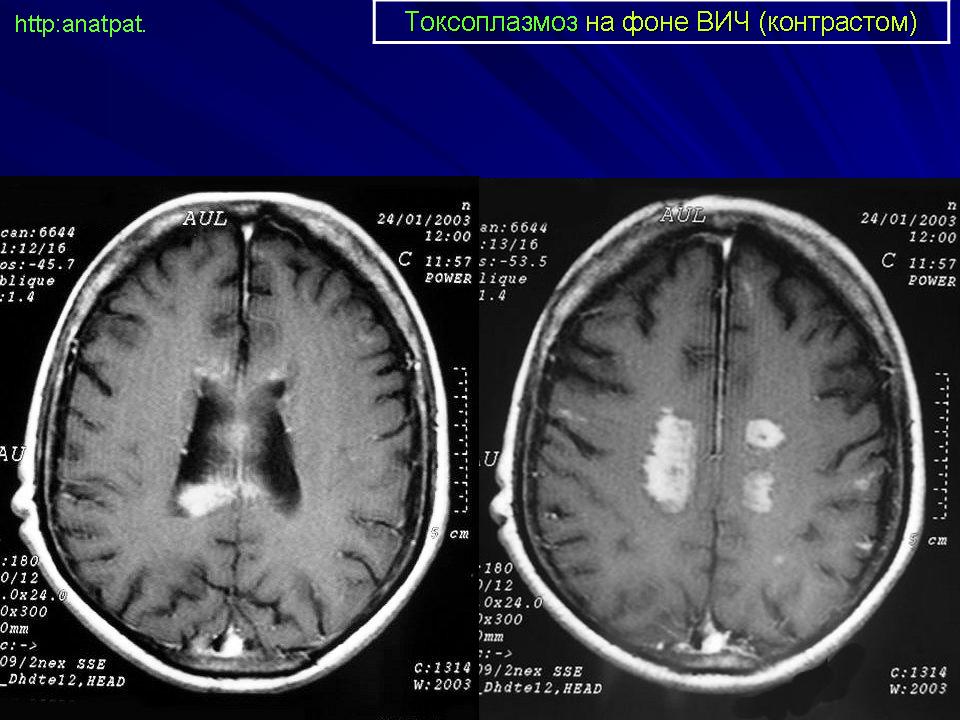

Церебральный токсоплазмоз.

Токсоплазмоз у ВИЧ - инфицированных

Церебральный токсоплазмоз

Neurotoxoplasmosis

Дифференциальная диагностика изображения